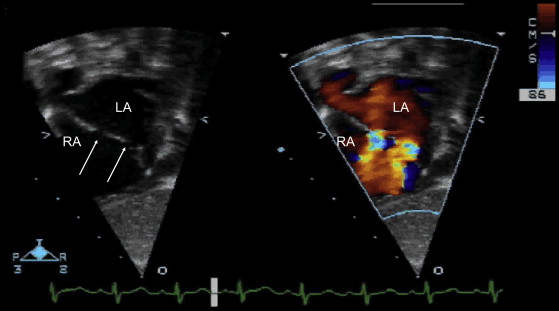

Predischarge Transthoracic Echocardiography after Surgery for Congenital Heart Disease: A Routine with a Reason?

Source: Predischarge Transthoracic Echocardiography after Surgery for Congenital Heart Disease: A Routine with a Reason? – Journal of the American Society of Echocardiography